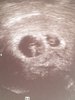

Dwa bijace[emoji173]️[emoji173]️Zobacz załącznik 906756

Jeszcze tutaj gratulacje kochana! Jejuuuu! Jak się cieszę.Dwa bijace[emoji173]️[emoji173]️Zobacz załącznik 906756

dalej się ładnie dzielą i dalej są 3 moje serduszka